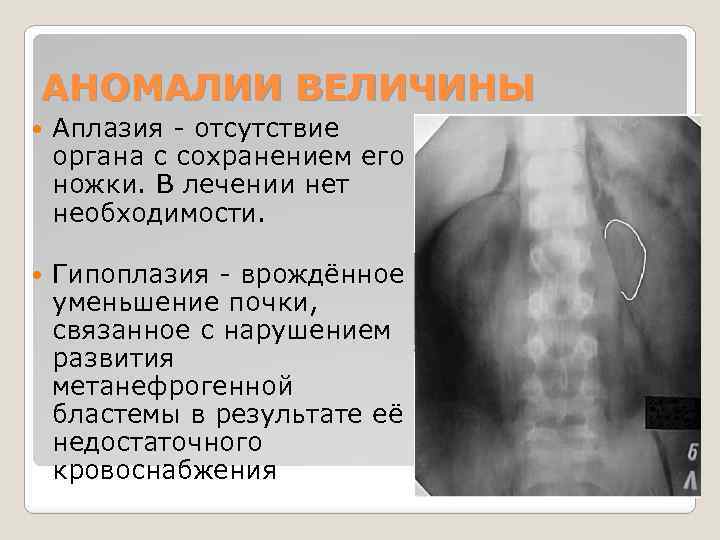

АНОМАЛИИ ВЕЛИЧИНЫ Аплазия - отсутствие органа с сохранением его ножки. В лечении нет необходимости. Гипоплазия - врождённое уменьшение почки, связанное с нарушением развития метанефрогенной бластемы в результате её недостаточного кровоснабжения

АНОМАЛИИ ВЕЛИЧИНЫ Аплазия - отсутствие органа с сохранением его ножки. В лечении нет необходимости. Гипоплазия - врождённое уменьшение почки, связанное с нарушением развития метанефрогенной бластемы в результате её недостаточного кровоснабжения